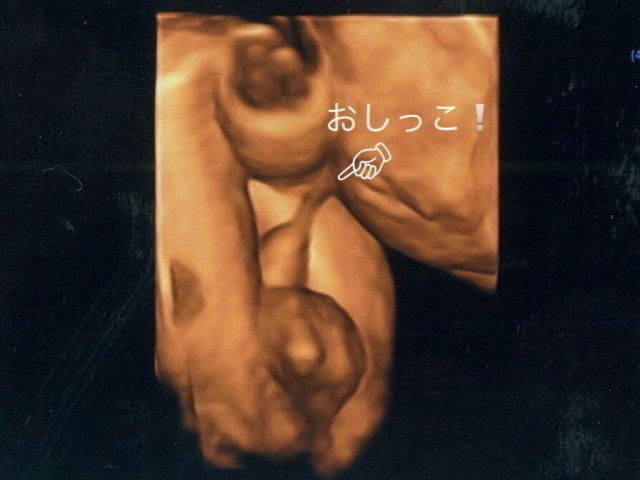

おなかの中で赤ちゃんがおしっこをしてる現場を激写!

「写真は妊娠8カ月の胎児が、おしっこをしているところを激写した3D超音波写真! おちんちんの先から出ているものがおしっこです。

赤ちゃんは子宮の中で、自分の周りを満たしている羊水を飲んで→おしっこを出す、ということを繰り返して、外の世界に出たときの練習をしています。赤ちゃんのおしっこは老廃物や菌が含まれない、きれいなもので、再び羊水になります」